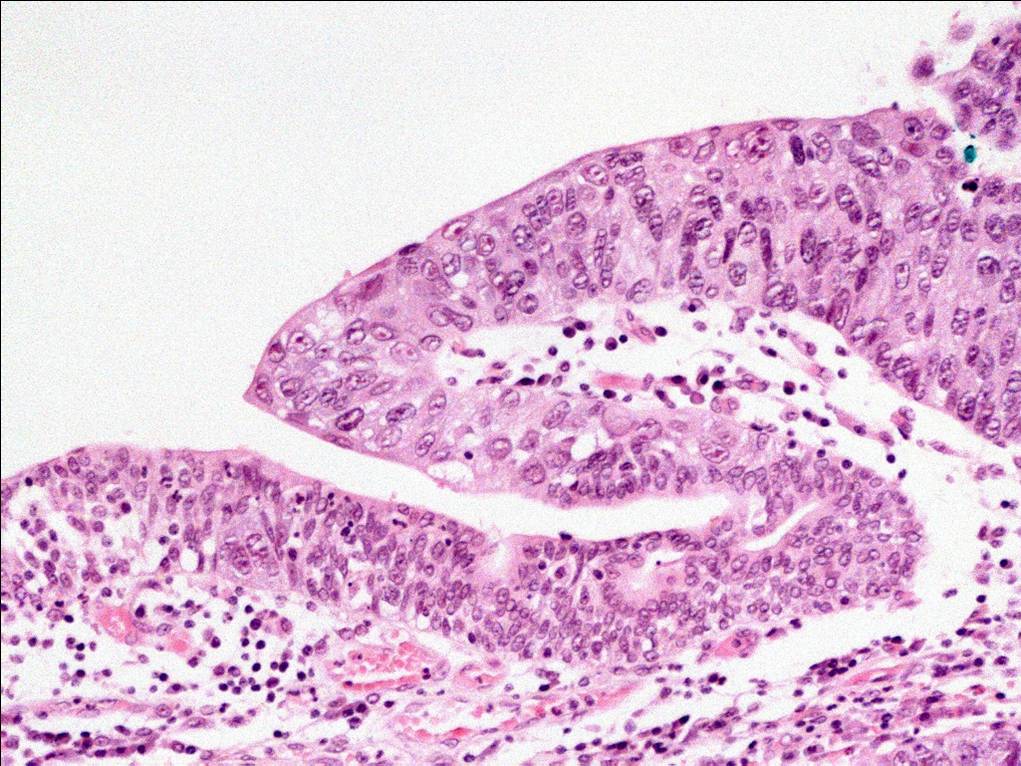

Bladder Flat Lesions

Case ID: 164